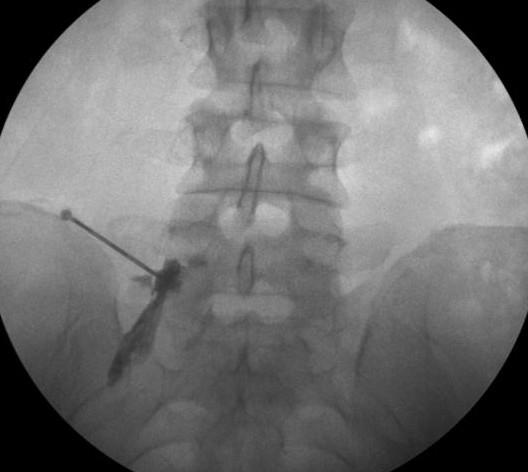

Durante o procedimento de infiltração na coluna, o paciente é posicionado de maneira adequada e pode receber anestesia local ou sedação para maior conforto. Utilizando técnicas de imagem, como fluoroscopia ou ultrassonografia, o médico guia uma agulha fina até o local específico da coluna vertebral onde a dor é originada.

Uma agulha é inserida através da pele, com auxílio de Raios-X, até a emergência da raiz nervosa no forâmen intervertebral desejado para a injeção de anestésico e corticóides.

A exata posição da agulha é confirmada com injeção prévia do meio de contraste, que traça o trajeto exato da raiz estudada.